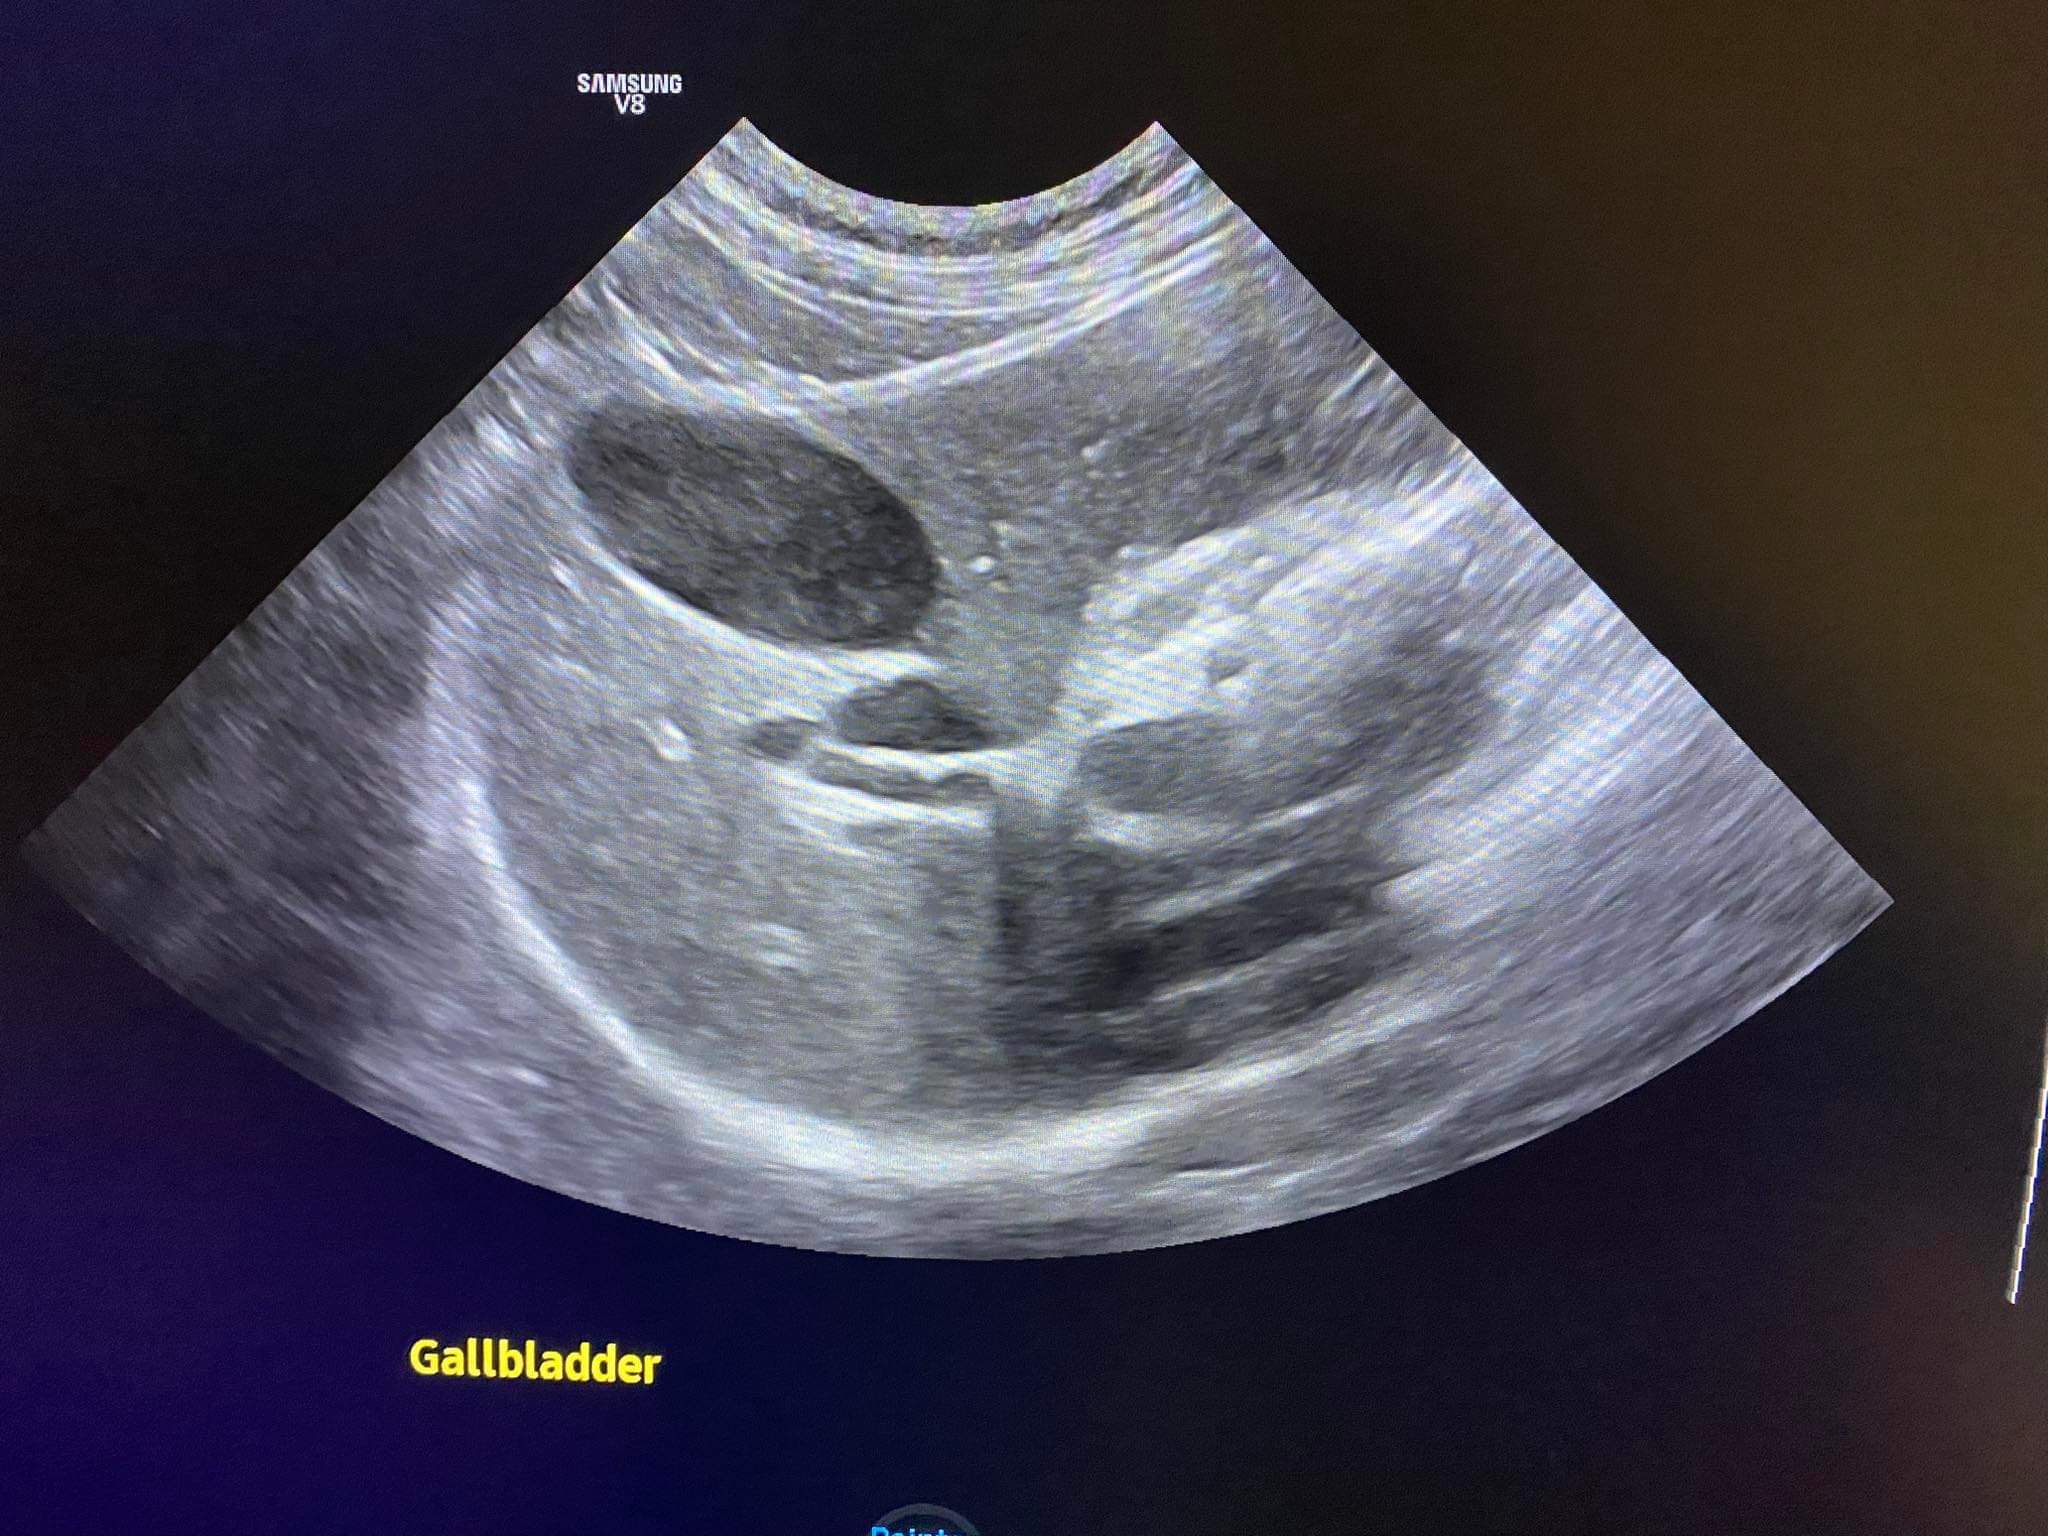

Going to do an abdomen u/s to check on his inner issue.

140pm u/s results r out:

dog attack internal injury possibility increased.

Bladder inside also look like got old blood clot.

Liver now is due to he is in pain/ not eating.

Otherwise intestinal tracts fine, so his is not gastro issue. Is internal injury issue.

Conclusion: it’s highly likely that it’s dog attack. Trauma to the spleen and bladder and pancreas that cost pancreatitis now.